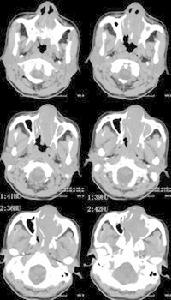

基本診斷

非何杰金氏淋巴瘤對放療及化療敏感,是可治癒性腫瘤,因此早期的診斷非常重要。對於特殊表現的非霍奇金淋巴瘤,臨床表現多種多樣應提高對本病的警覺,特殊表現的非霍奇金淋巴瘤診斷多為晚期,呈侵襲性病程,多有全身症狀發熱、盜汗及衰弱等,療效差。非霍奇金淋巴瘤病理組織學特點:

4.出現較多病理分裂相。活體組織病理學檢查是非霍奇金淋巴瘤鑑別診斷及確診的主要依據,必不可少。與造血系統腫瘤鑑別還需進行骨髓細胞學檢查。

目前本病的病理學診斷已發展為在傳統的形態學基礎上結合免疫學標誌、細胞遺傳學及基因標誌的多指標綜合診斷,從而提高診斷的正確率。